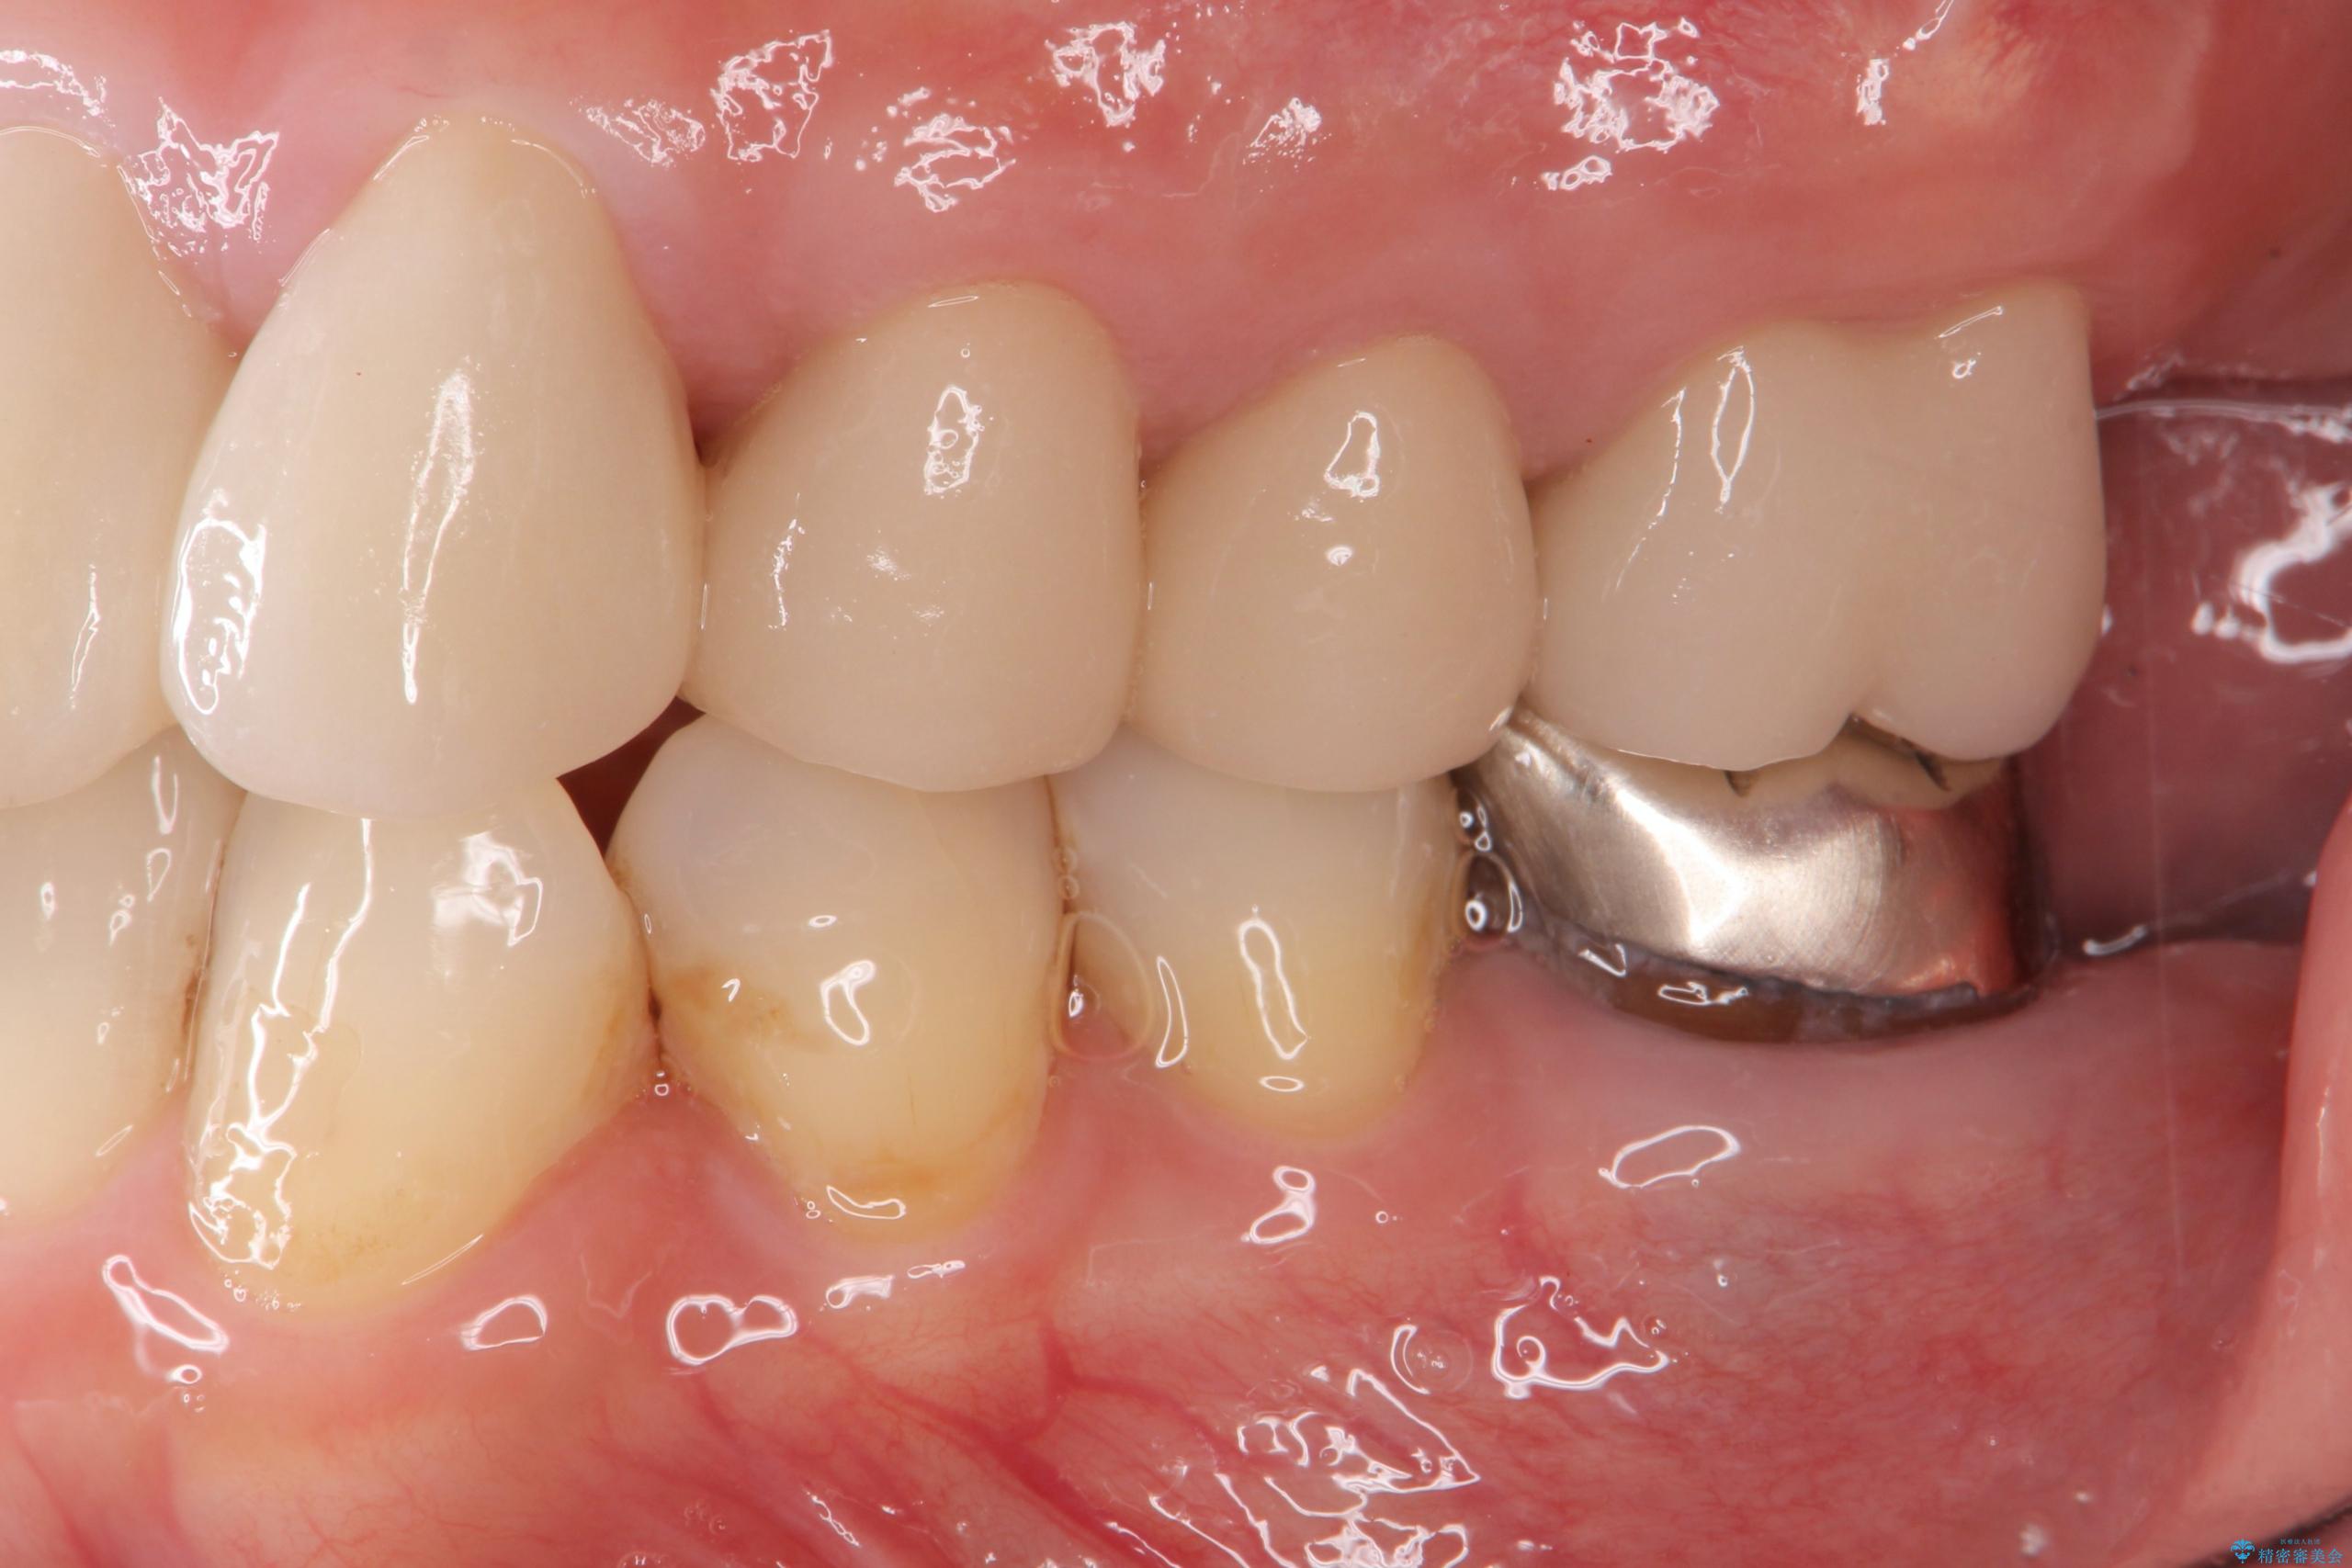

他院での治療の途中で通院をやめてしまい、当院で治療の続きを希望された患者様です。

クラウンが装着されておらず、つぎはぎだらけの処置歯を、精度の高いセラミッククラウンを用いて歯ブラシのしやすい環境整備を行っていきます。